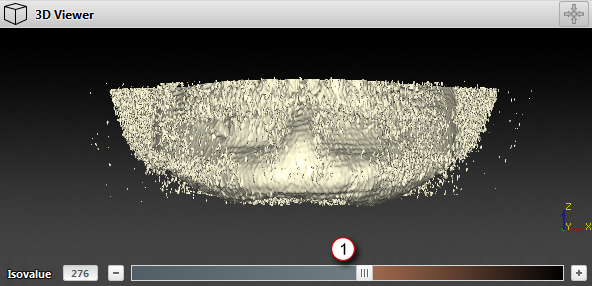

The model is too noisy. What can I do to reduce artifacts?

If the predefined lower threshold does not provide the level of detail desired, you must identify a threshold that is high enough to minimize the noise, but low enough to optimize the bone surface.

1. Isovalue slider

When a threshold of 270, for example, seems to be too low because too much noise appears, the threshold must be raised. At 900, the isovalue might seem to be too high because parts of the bone start disappearing and are not covered by the orange mask. A threshold of approximately 400 seems to be correct as there is only a limited amount of noise and all the bone surfaces are colored orange. Therefore, the appropriate threshold must be between 400 and 700.

The numbers mentioned above are only an example. Each 3D model should be considered individually.

‒ Drag the isovalue slider to the left or right to define the optimal isovalue.

‒ Enter the value in the isovalue input box.